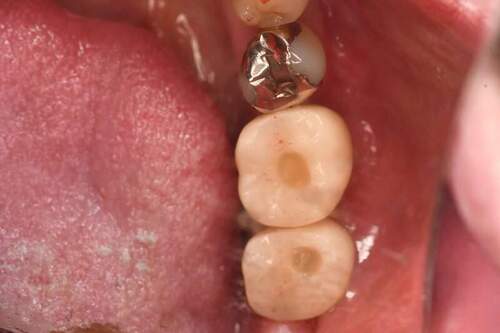

口腔内写真

- Befor

- After

| 年齢 | 50代・男性 |

|---|---|

| 主訴 | 左上7番 左下5番7番 |

| 治療内容 | ・インプラント埋入 ※1:GBR(骨造成)・・・骨再生誘導法。骨の高さや厚みを人工骨や人工膜などを使用し再生する方法 |

| 治療費 | 合計:1,809,500円(税込) ■内訳 ・左上7番 ・左下5番7番 |

| 治療期間 | 左上7番約1年 左下5番7番約10ヵ月 |

| 治療方針 | 左上7番は昔他院で被せものをしており、被せものの中が歯ぐきの中まで虫歯になっていたため抜歯せざるを得ない状態だった。抜歯と同時に骨造成を行い、骨が出来るまで4ヵ月待ってからインプラントを埋入した。 ※2ポンティック・・・歯のない部分を補うダミーの歯。 |

| 担当者所見 | 元々金属の被せものが多く入っていたため、2次カリエス※3が多かった。今回は金属ではなく、ジルコニアを使用し、2次カリエスにならないよう、患者様にはブラッシング指導とメンテナンスの重要性をお伝えした。 ※3二次カリエス・・・詰め物や被せものを入れた歯が虫歯になること。 |